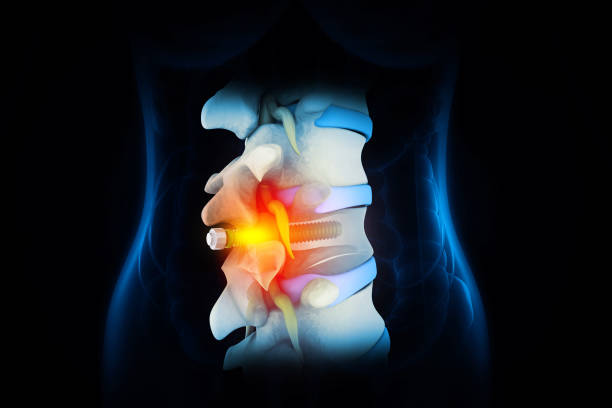

척추관협착증에 대한 이해

척추관협착증은 척추 주변의 근육과 인대가 퇴행하여 척추관 내 황색 인대가 비정상적으로 부풀어 오르면서 발생하는 퇴행성 척추질환 중 하나입니다. 이 질환은 가까운 거리도 통증으로 인해 걷기가 어려워지는 특징을 가지고 있으며, 새벽에 다리에 통증을 느끼는 경우가 많습니다.

척추관협착증은 다른 척추 질환에 비해 퇴계 정도가 매우 심한 질환으로, 퇴행이 심할수록 근육과 인대가 더욱 뭉쳐지고 더 많은 압력을 가하게 됩니다. 이 때문에 근육과 인대를 풀어주는 것이 중요하며, 이를 위한 가장 적합한 운동이 걷기입니다.